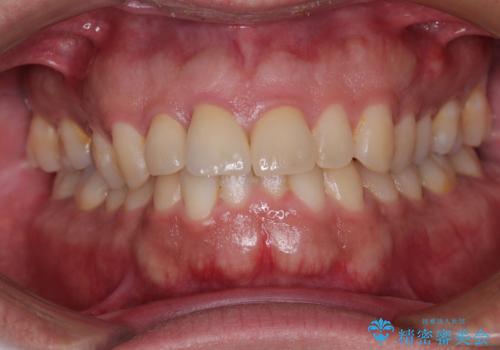

- 自転車で転んで前歯をぶつけたとのことで来院された患者様です。

事故後に受診した病院の歯科にて前歯2本の欠損した部分を修復されておりましたが、見た目が気になるとのことで、オールセラミッククラウンにて補綴治療を行うこととしました。

神経組織の状態を確認しましたが、片方は正常反応でしたが、他方は鈍い反応しかありませんでした。

速やかにオールセラミッククラウンにて補綴治療を行い、数ヶ月後に再度神経組織の状態を確認して、失活しているようであれば根管治療を行うこととしました。

しかしながら、補綴治療後間もなく再度自転車事故に遭い、追加1本の計3本を損傷する事態となりました。

再度損傷した3本は完全に失活した状態であったため、速やかに根管治療を行い、オールセラミッククラウンにて補綴治療を行うこととしました。